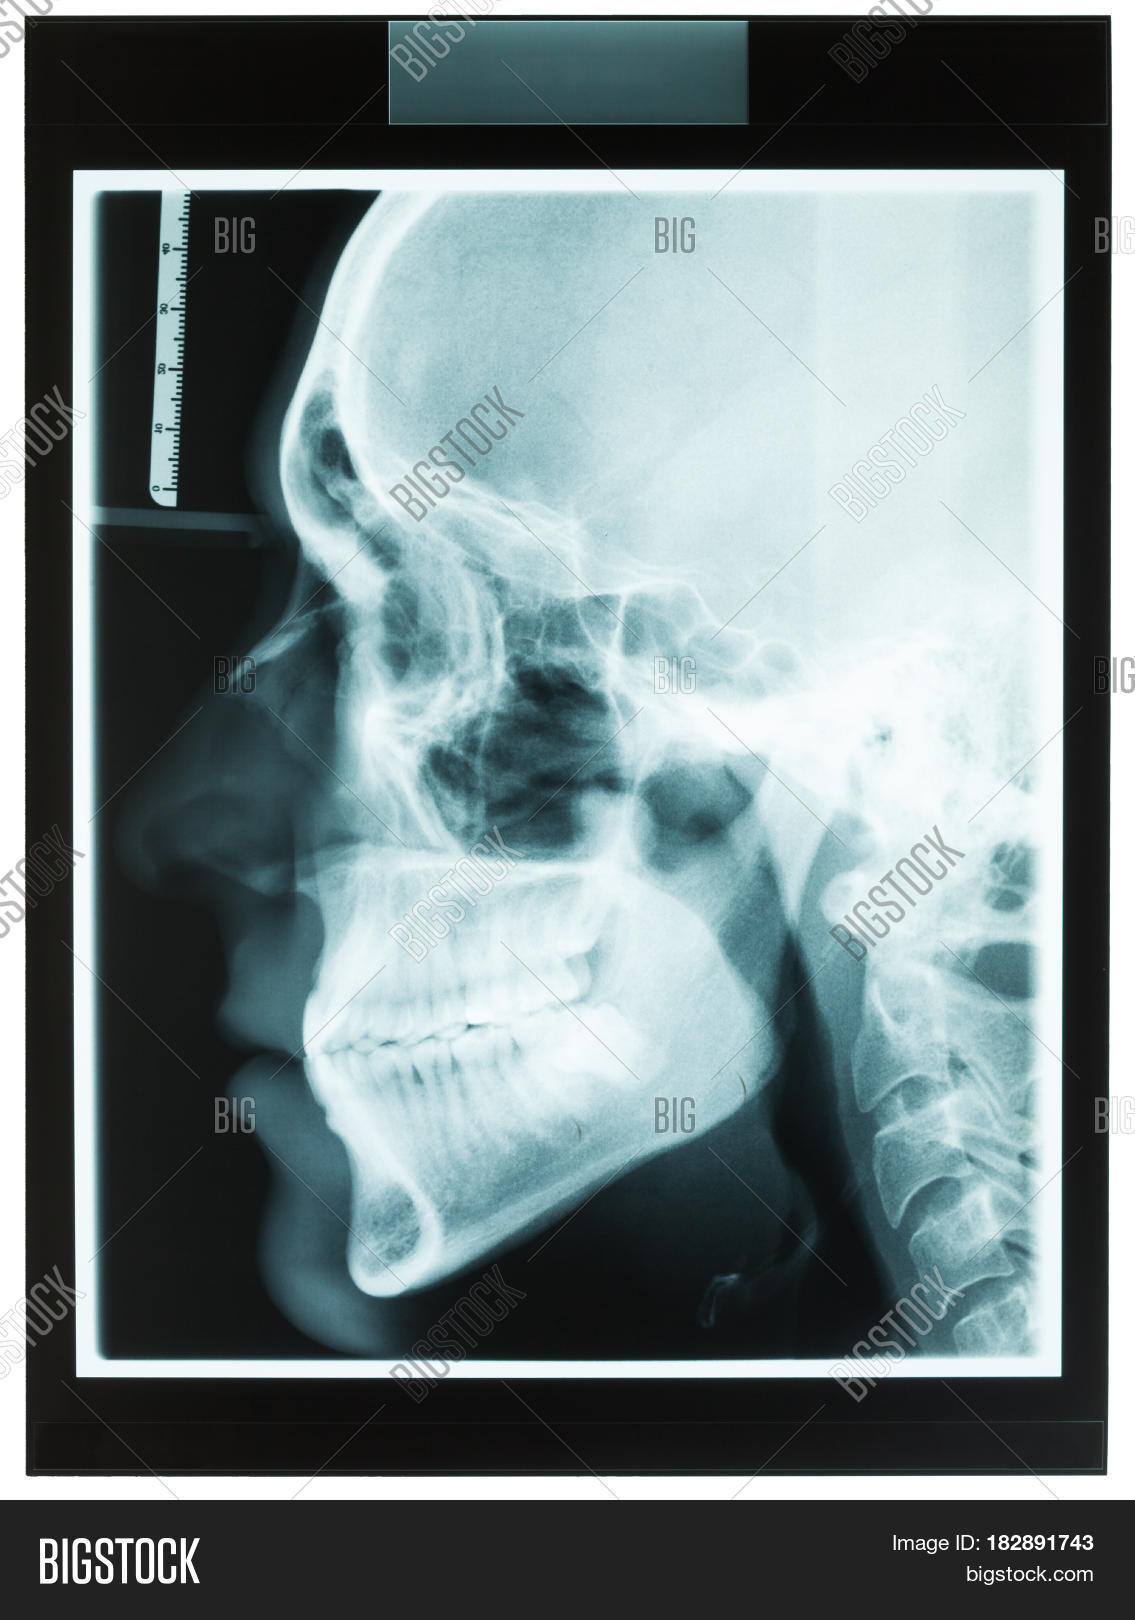

From www.bigstockphoto.com

Profile Xray Man's Jaw Image & Photo (Free Trial) Bigstock Jaw X Ray Views A properly positioned radiograph of the face and mandible shows the relationship between the bony structures and soft tissues of. Imaging plays a key role in the characterization of a variety of jaw lesions, and radiologists must be familiar with Proper characterization of jaw abnormalities is essential to ensure appropriate patient care and reduce morbidity. The temporomandibular joint (tmj) is. Jaw X Ray Views.